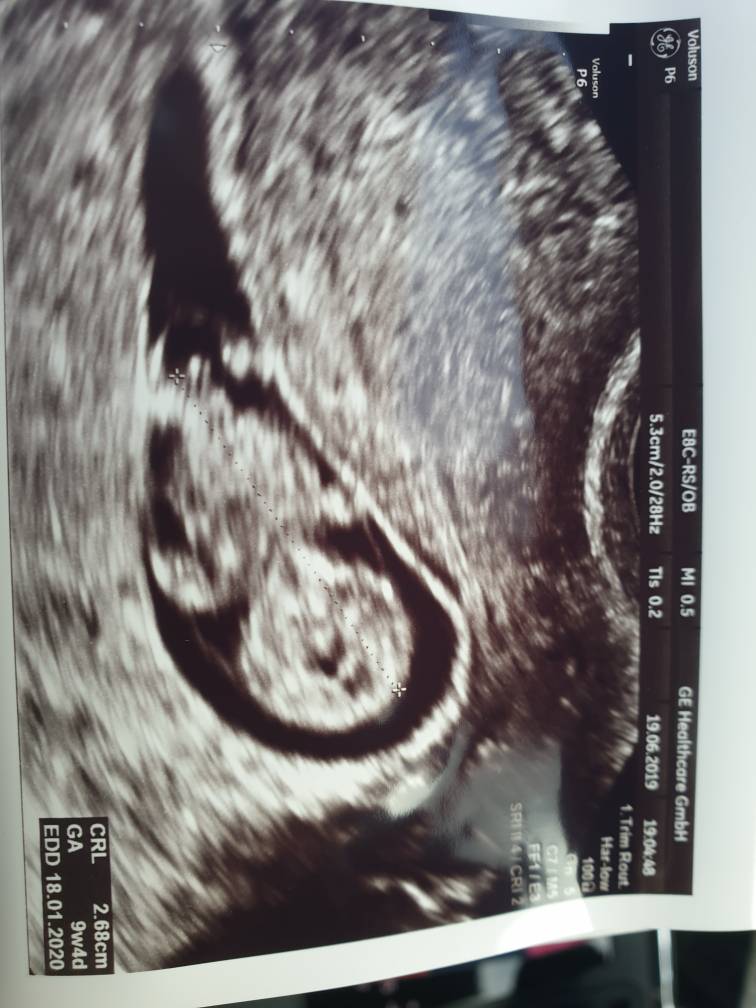

Według om 11t4d a usg 12t0d :) maluch wystarczająco duży do usg prenatalnego, aaaale spał i za nic nie chciał współpracować [emoji85] próbowała ginka go obudzić, ale pomachał nogą i najlepiej to by się jeszcze tyłeczkiem obrucił [emoji12][emoji1787] za 2 tygodnie idę do jej koleżanki bo ona ma urlop niestety. Według niej wszystko okej, opisała mózgowie itd :) no ale lepiej jeszcze sprawdzić jak będzie maluch większy.